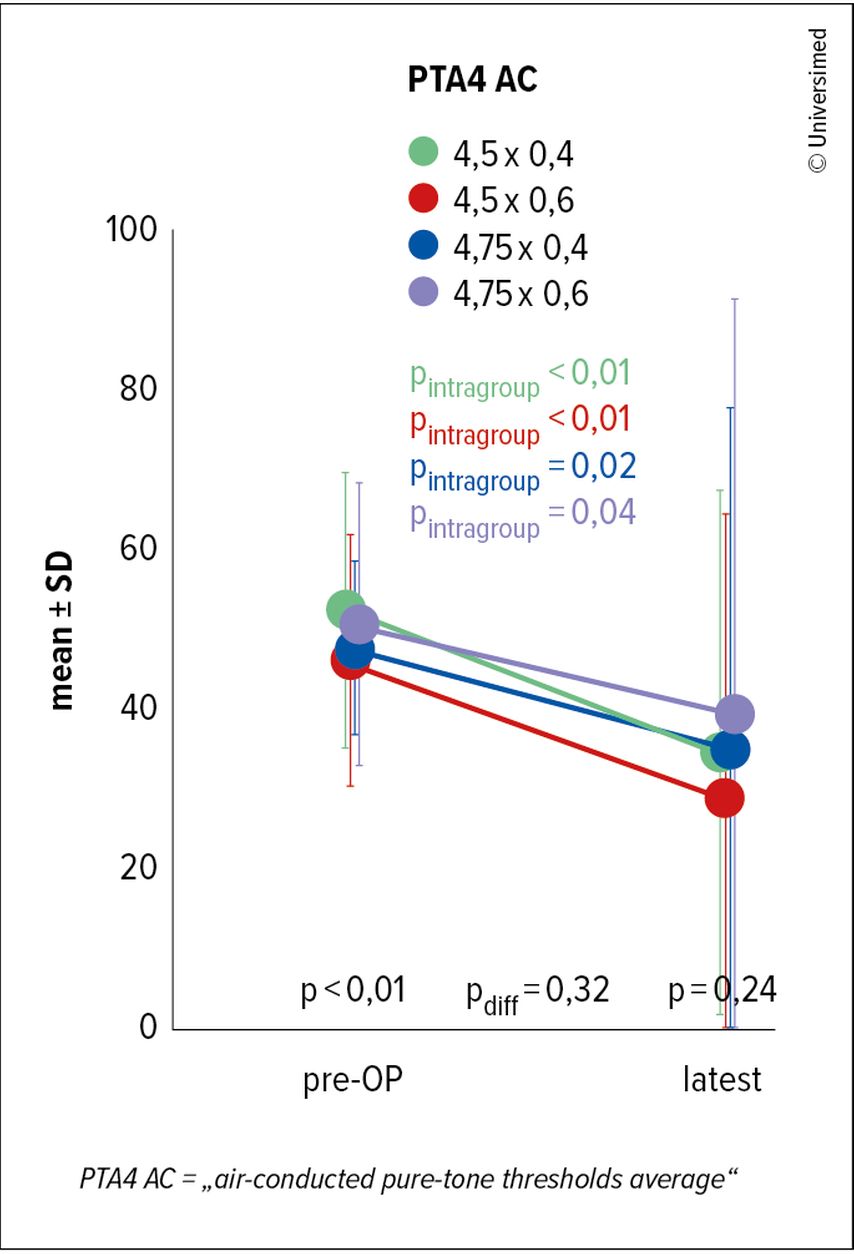

Im Vergleichprä- vs. postoperativkonnte eine signifikante Verringerung der Luftleitungsschwelle von im Durchschnitt knapp 16dB, von präoperativ 50dB auf postoperativ 34dB, verzeichnet werden (Abb. 5).